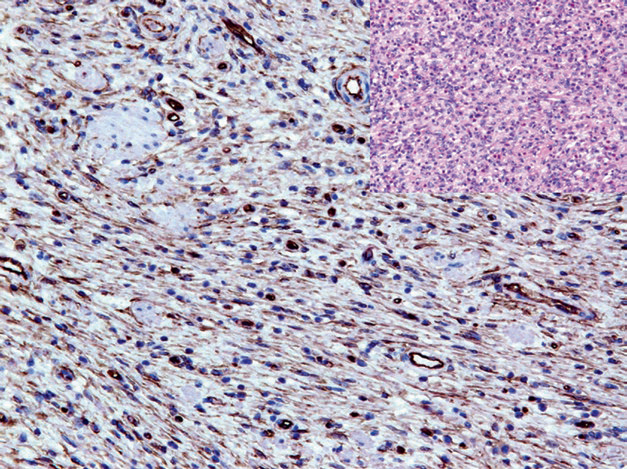

图2. 胃肠道间质瘤,CD117强阳性。

阳性表达模式:细胞膜/胞质

推荐阳性质控组织:脑组织

CD117是酪氨酸激酶生长因子受体III家族成员,具体由细胞外结构域、跨膜结构域、细胞内激酶区三部分构成。该家族成员还有PDGFR-α、巨噬细胞集落刺激因子、FMA样酪氨酸激酶3。正常情况下,CD117的活化发生于干细胞因子结合以后,参与造血细胞、肥大细胞、生殖细胞、黑素细胞(melanocytes)、肠道Cajal细胞的分化;因此日常工作中,CD117的表达范围非常广泛,可用作多种肿瘤的诊断标记,如精原细胞瘤、肥大细胞瘤、慢性及急性髓细胞性白血病、胸腺瘤、腺样囊性癌、部分急性T淋巴细胞白血病、多种恶性黑色素瘤。CD117的表达可见于90%以上的胃肠道间质瘤;约80%的胃肠道间质瘤具有c-Kit基因的单个或多个活性突变,主要位于11号外显子,少见情况下可见于9号、13号、17号外显子。CD34及DOG1的共表达也是该肿瘤特征性免疫组化表现。5-8%的胃肠道间质瘤还会有PDGFR-α基因的突变,且一般CD117阴性;这类肿瘤常呈上皮样形态,且免疫组化多为PDGFR-α和/或DOG1的阳性。